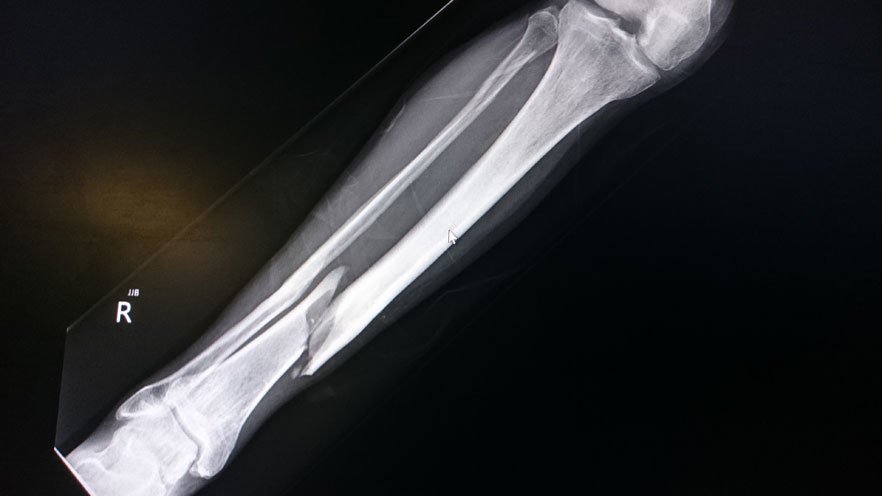

Bones are the hardest, sturdiest parts of our bodies. But trauma — such as from a fall, car accident, or sports injury — can break or dislocate even the strongest bones.

bone fracture